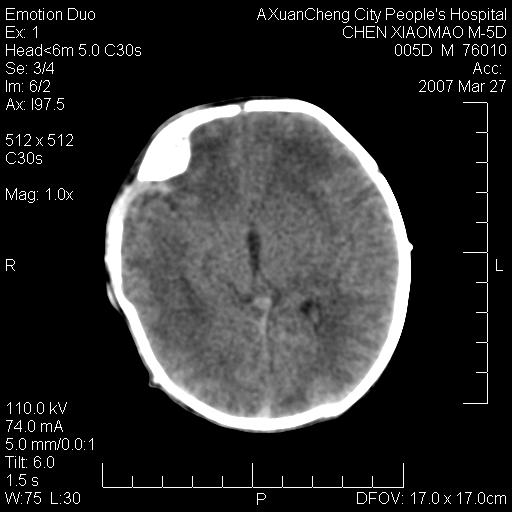

大家看看可有出血?另外枕骨中央是骨缝还是骨折

缝是正常的,但患儿有hie

大家看看可有hie ?还有左侧枕部胡形高密度ct为45~53hu,可有硬膜下血肿?

左颞枕部有出血,枕骨有骨折